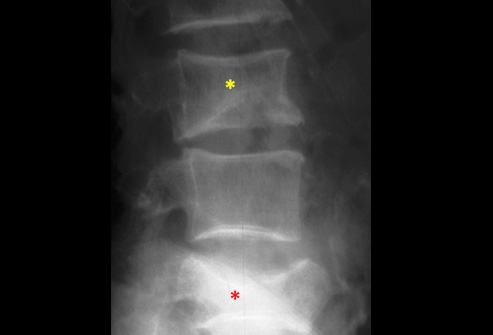

Рентгеновские снимки и медицинские изображения компрессионных переломов